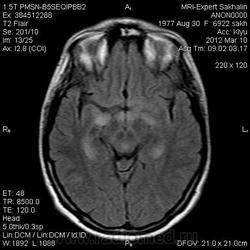

Направительный диагноз:головная боль напряжения.

Краткий анамнез заболевания, жалобы: головные боли,снижение памяти, раздражительность, снижение аппетита в течение 3-х месяцев.

Подозреваю демиелинизацию,гиппокампальный склерз ( тогда базальные ядра и ножки при чем?),ишемические проявления -не знаю!Помогите , пожалуйста, начинающему доктору!

Лимбический энцефалит? Паранеопластический процесс? А где диффузионные программы- не помешают. Нужно подумать (или спросить у ннемо, например))).

Написала дифф.ряд: лимбический энцефалит, лимфому ЦНС, герпетический энцефалит.

С лимфомой верифицированной не встречался, картина не противоречит паранеопластическому или герпетическому энцефалиту. Склероз гиппокампов: нет уменьшения их размеров, зоны изменений сигналов гиппокампами не ограничиваются, есть кроме височных долей и в ножках мозга, опять же накопление контраста.

Женщина 1977 года рождения.Со слов мужа , около 3/х мес. назад начались головные боли, снижение памяти, раздражительность снижение аппетита.Перенесла какую-то инфекцию типа ОРЗ.С ней разговаривать трудно-мало что помнит.На асоциальную , наркоманку не похожа-приличная с виду женщина.Неврологический статус хотела выяснить у лечащего врача по телефону, но она живет в районе,и телефон не указала .Визуально-неврологический статус без особенностей.В направлении-головная боль напряжения .Нет указаний -на что обратить внимание.

Ишемические изменения и темпоральный склероз - нет.

Для И.Бондаренко - вы все правильно указали - гипер- в Т2W, а также гипо- в Т1W, + очаги накопления контраста

Есть и давно подтвержденное понятие паранеопластический лимбический энцефалит - как вариант примерно так и будет выглядеть.

В данном случае больше данных за воспалительный энцефалит - есть синусит (не нравиться гиперинтенсивное включение парацентрально в пазухе -грибок????) .

С учетом накопления контраста да и по локализации однозначно не опухоль, не инсульт, не травма. Из классики да действительно герпес любит виски, также и иные вирусные могут быть (этиологию иной раз не угадаешь - бессмыслено), может быть и тбс. но сос четов не сбрасывал бы паранеопластический - тем более женщина да и контраст накопила как бы не молочка?? Ну и совсем чтоб запутать нет ли В20? только на внешний вид и на мужа не надо ориентироваться - у нас и у врачей и у студентов мед вузов бывает - пройденный этап(((

Была у нас пациентка (картинки предоставить не могу , так как поезд ушел) , картина была один в один , только в меньшей степени выраженности. Тоже возникло после перенесенной ОРВИ, после лечения приходила на контроль - мр- сигнал вернулся к норме. Так что согласна с энцефалитом. При паранеопластическом процессе все же более четкие границы , я так думаю. и распостраненность несколько другая..